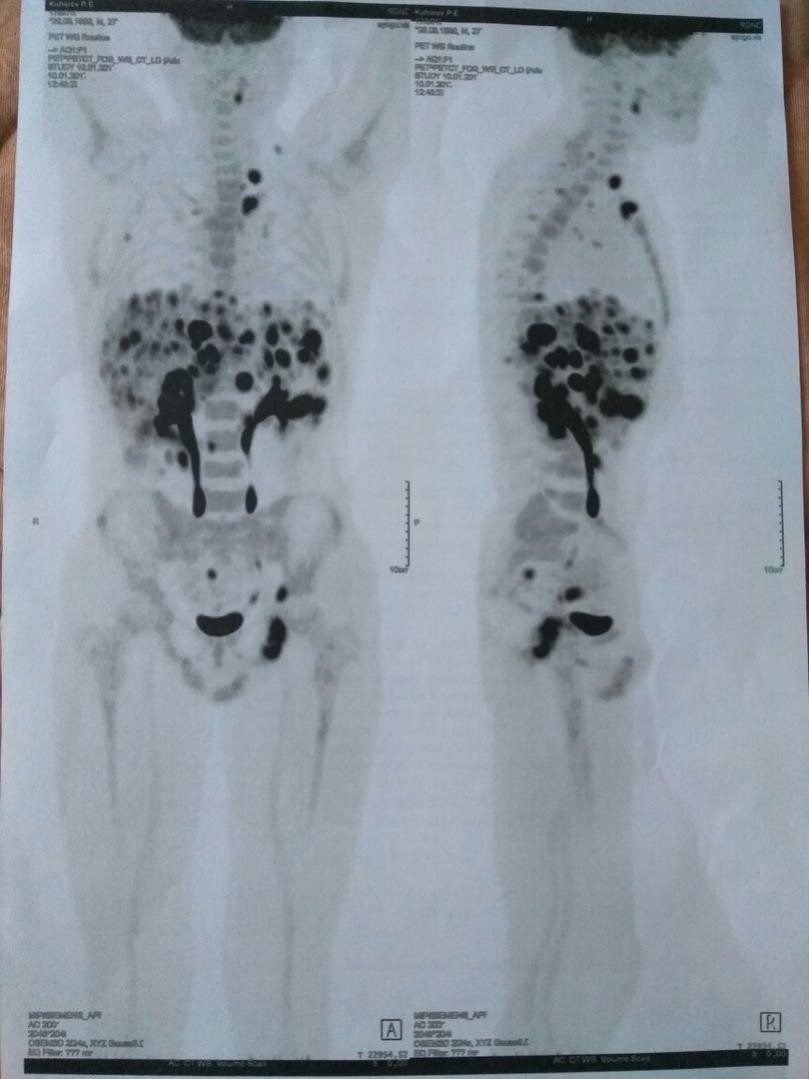

Преждевременная паника ни к чему. Делайте обследования и многое прояснится. ПЭТ КТ хорошо показывает накопление препарата в лимфоузлах.

Изображения

Тип файла: jpg BrE8u5Gk5go.jpg (67.7 Кб, 509 просмотров)